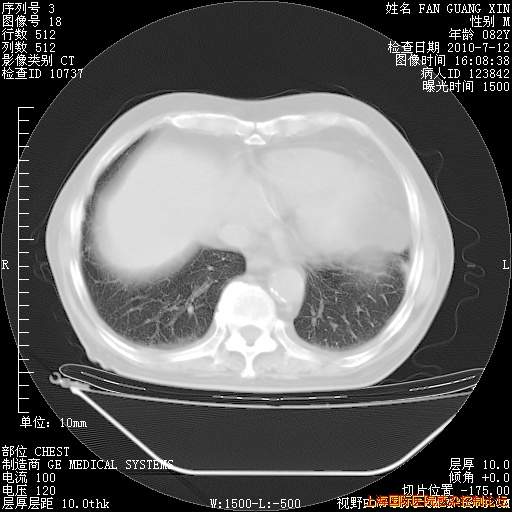

今天复查CT

今天CT

整整相隔30天的肺部CT好像有所好转啊。甲强龙减量第3天,需要观察体温。